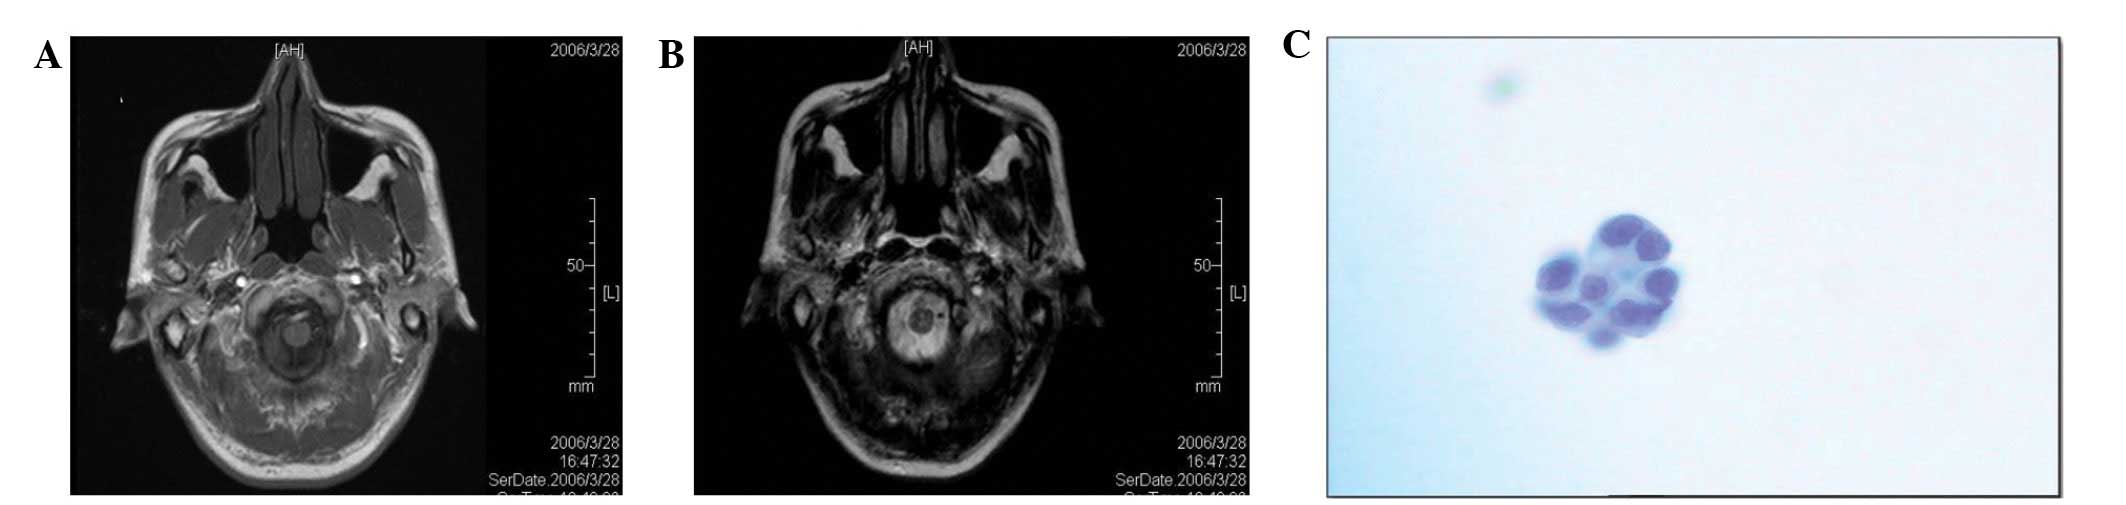

tightness and pain. In March 2006, a chest X-ray showed a shadow in

the right lower lung with a small amount of pleural effusion. The

chest computerized tomography (CT) showed a 2×1.5 cm block shadow

in the right lower lung, a medium dose pleural effusion in the

right chest cavity and certain mediastinal lymph nodes with

calcification (Fig. 1A and B). The

emission CT (ECT) showed numerous bone metastases. On March 27th,

2006 (week 0), a tube was placed in the right chest cavity and

drained 2400 ml of the pleural effusion. The entire pleural

effusion was drained after 3 days and consisted of ∼3,020 ml in

total. Adenocarcinoma cells were identified in smears of the

pleural effusion (Fig. 1C) and the

diagnosis from a Board Certified Pathologist was determined as that

of a right lower lung adenocarcinoma (T4N2M1, stage IV). Following